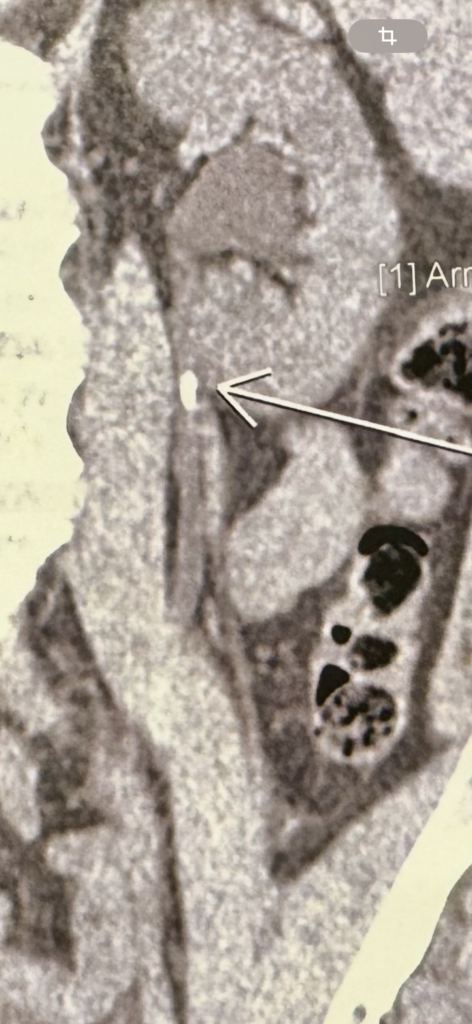

Ασθενής άρρεν 43 ετών με λιθίαση 0,8 εκ. αριστερής πυελοουρητηρικής συμβολής(το σημείο όπου ενώνεται ο νεφρός με τον ουρητήρα).

Ο λίθος προκαλεί απόφραξη και διάταση του νεφρού που συνοδεύεται από έντονο πόνο(κολικός νεφρού).

Δείτε την εικόνα από την αξονική τομογραφία